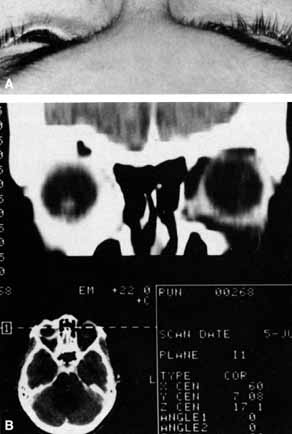

Ophthalmoscopy can be very helpful in orbital diagnosis. Optic disc edema may be caused either by papilledema (increased intracranial pressure) (Fig. 11A), papillitis (anterior optic neuritis) (Fig. 11B), or vasculitis (e.g., lupus erythematosus, sarcoidosis, Wegener's granulomatosis, and giant cell arteritis) (Fig. 11C).12 Papilledema (Fig. 11A) is usually present with near-normal visual function, although some patients may lose vision.9 In contrast, papillitis (Fig. 11B) characteristically leads to reduced visual function, commonly is associated with orbital pain, and is associated with inflammatory cells in the vitreous overlying the disc. Optic disc vasculitis (Fig. 11C) may be present with other findings of vasculitis, and commonly is associated with poor acuity and evidence of vascular occlusion (e.g., cotton-wool spots, hemorrhages). The differential diagnosis of the swollen, erythematous disc is discussed elsewhere in these volumes.

Fig. 11 A. Papilledema caused by pseudotumor cerebri. Visual acuity is 20/15 and the visual field is normal. B. Papillitis of anterior optic neuritis. Visual acuity is 20/400 with a relative afferent pupillary defect and a central scotoma. C. Vasculitis of optic disc caused by lupus erythematosus. Visual acuity is 20/200, there is a relative afferent pupillary defect, and a cecocentral scotoma. Note cotton-wool spots.